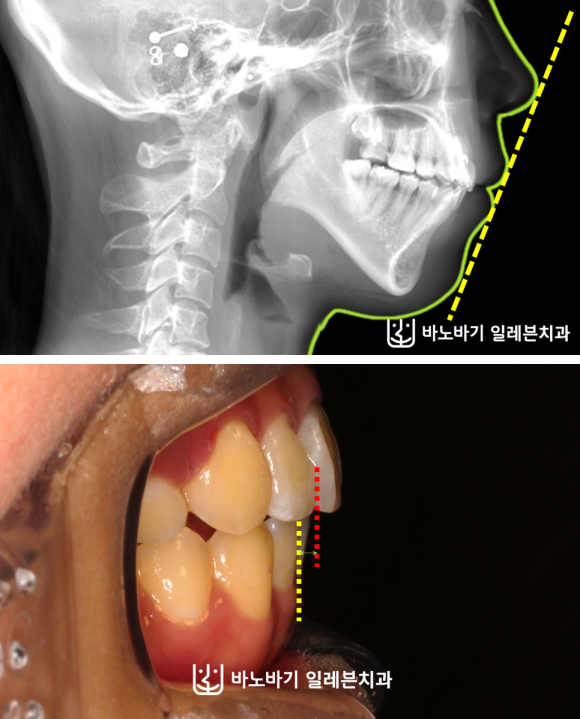

아래턱이 위턱보다 뒤에 있고, 상악 전치의 전방경사로 인해 입이 잘 다물어지지 못하는 증상을 보이고 있으셨습니다.

물론 외관상 단점도 관찰됐는데, 돌출입이 뚜렷한 편이었습니다.

게다가 입을 억지로 다물면서 입술에 힘을 주다 보니, 하악 이부 근육의 긴장감이 호두턱으로도 이어졌습니다.

무턱 때문에 발생하게 되는 전형적인 외모적 문제점이 이분에게서도 나타났습니다.

이밖에 앞니가 잘 닿지 못하며, 상악 우측 치열만 앞으로 나왔다는 점을 발견했습니다.

골격 불균형을 보완하기 위해 윗니 양쪽에 위치해 있는 제1소구치 2개를 발거하여 공간을 확보해주었습니다.

하악에서는 옆으로 누워버린 사랑니를 제거하였습니다. 상하로 각각 다른 곳을 뽑는 발치전략을 수립하였습니다.

이번 사례에서는 어떤 수술도 이루어지지 않았습니다. 상악 앞니의 전방경사를 적절한 수준으로 조정하면서, 전치부를 뒤로 움직였는데요.

이런 과정만으로 돌출입이 상당 부분 개선되었습니다. 윗니와 아랫니의 앞뒤간격도 굉장히 많이 줄어들었네요.

옆모습도 많이 좋아졌습니다. 입술이 자연스레 다물어지도록 만드는 데에 성공했습니다.